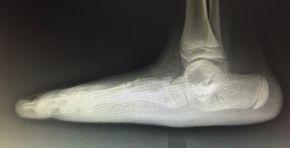

The image above compared to the image on the left, demonstrates a flat foot reconstruction achieved through bony procedures and is aimed at restoring the arch and maintaining joint motion.